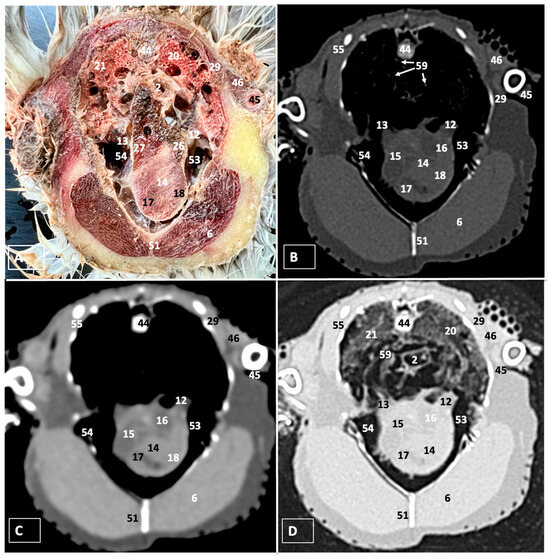

3. Results

3.1. Anatomical Dissections and Cross-Sections

3.2. Computed Tomography Images